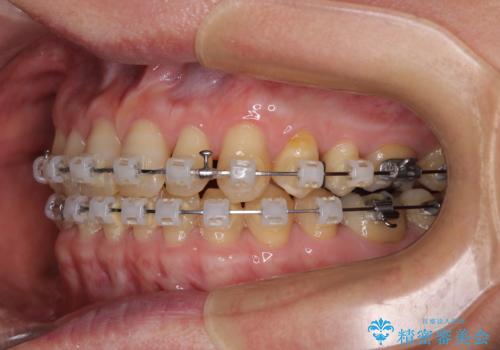

- 矯正装置

- クリアブラケット

- 前歯のデコボコと隙間の空いた歯列を気にして来院された患者様です。

下顎前歯が隠れるほどのディープバイトにより、強い咬合力と突き上げで上顎歯列に隙間が空いている状態でした。

手前に傾斜している奥歯をワイヤー装置で立ち上がらせ、咬み合わせの高さを挙上することで突き上げを解消し、空隙歯列を改善していくこととしました。